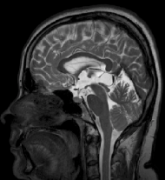

松果体区囊肿是恶性肿瘤吗?

松果体囊肿 是一种比较常见的先天性疾病。松果体是大脑中一个产生褪黑激素的小器官,褪黑激素帮助调节其他激素,维持身体的昼夜节律。而松果体囊肿是因松果体实质发生坏死所致...

松果体肿瘤一般多大?松果体瘤是良性还是恶性?

松果体肿瘤比较少见,主要生长在大脑中心区松果体位置,这将影响松果体功能的正常运行...